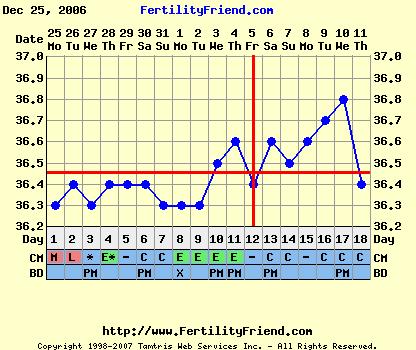

És tényleg, miért is mondod, hogy olyan rémes ez a görbe?! A mostani leesés miatt? Merthogy nekem még eddig egy ciklusban sem rajzolt a fertility ilyen határozott pé-es piros vonalat. Én mindig csak szaggatottat kapok.

Mo, hát, a görbéd valóban érdekes, reméljük, hogy semmiféleképpen nem a mensit mutatja a hőd leesése.

Hát, ez a görbe, ha már később volna néhány nappal, felérne egy pé-el! Remélem, még nem volna. Azért az kicsit korai lett volna. Meg az LH teszt sem jelezte. Bár a PG53 mutatott ezt-azt. Na, ezt a gondolatot gyorsan el is hesegetem magam elől!